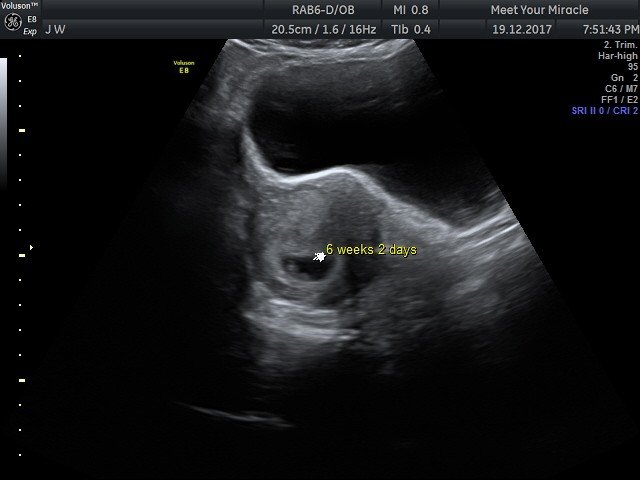

View beautiful baby scan images captured in our studios

Baby scan image 2